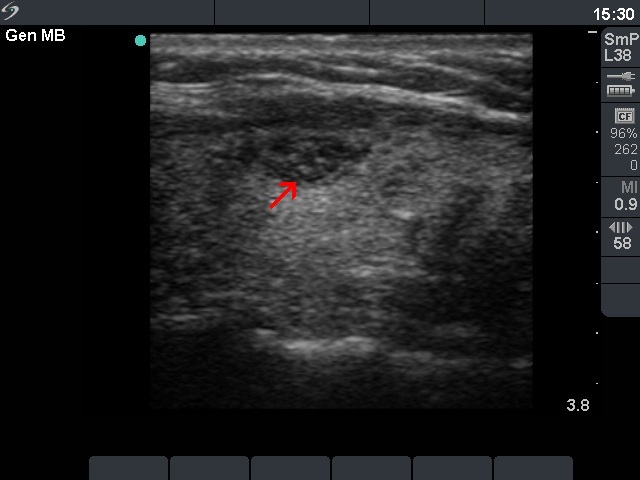

Follicular adenoma (histological diagnosis) - case 1056 |

Papillary carcinoma (histological diagnosis) - case 1074 |

The presentation of the granules is similar in these cases. However the benign lesion has several granules with dorsal tail, therefore these correspond more likely to comet-tail artifacts than to punctate echogenic foci. On the other hand, the complex structures in the malignant nodules are composed of multiple granules. It is worth comparing the figures marked with arrows.